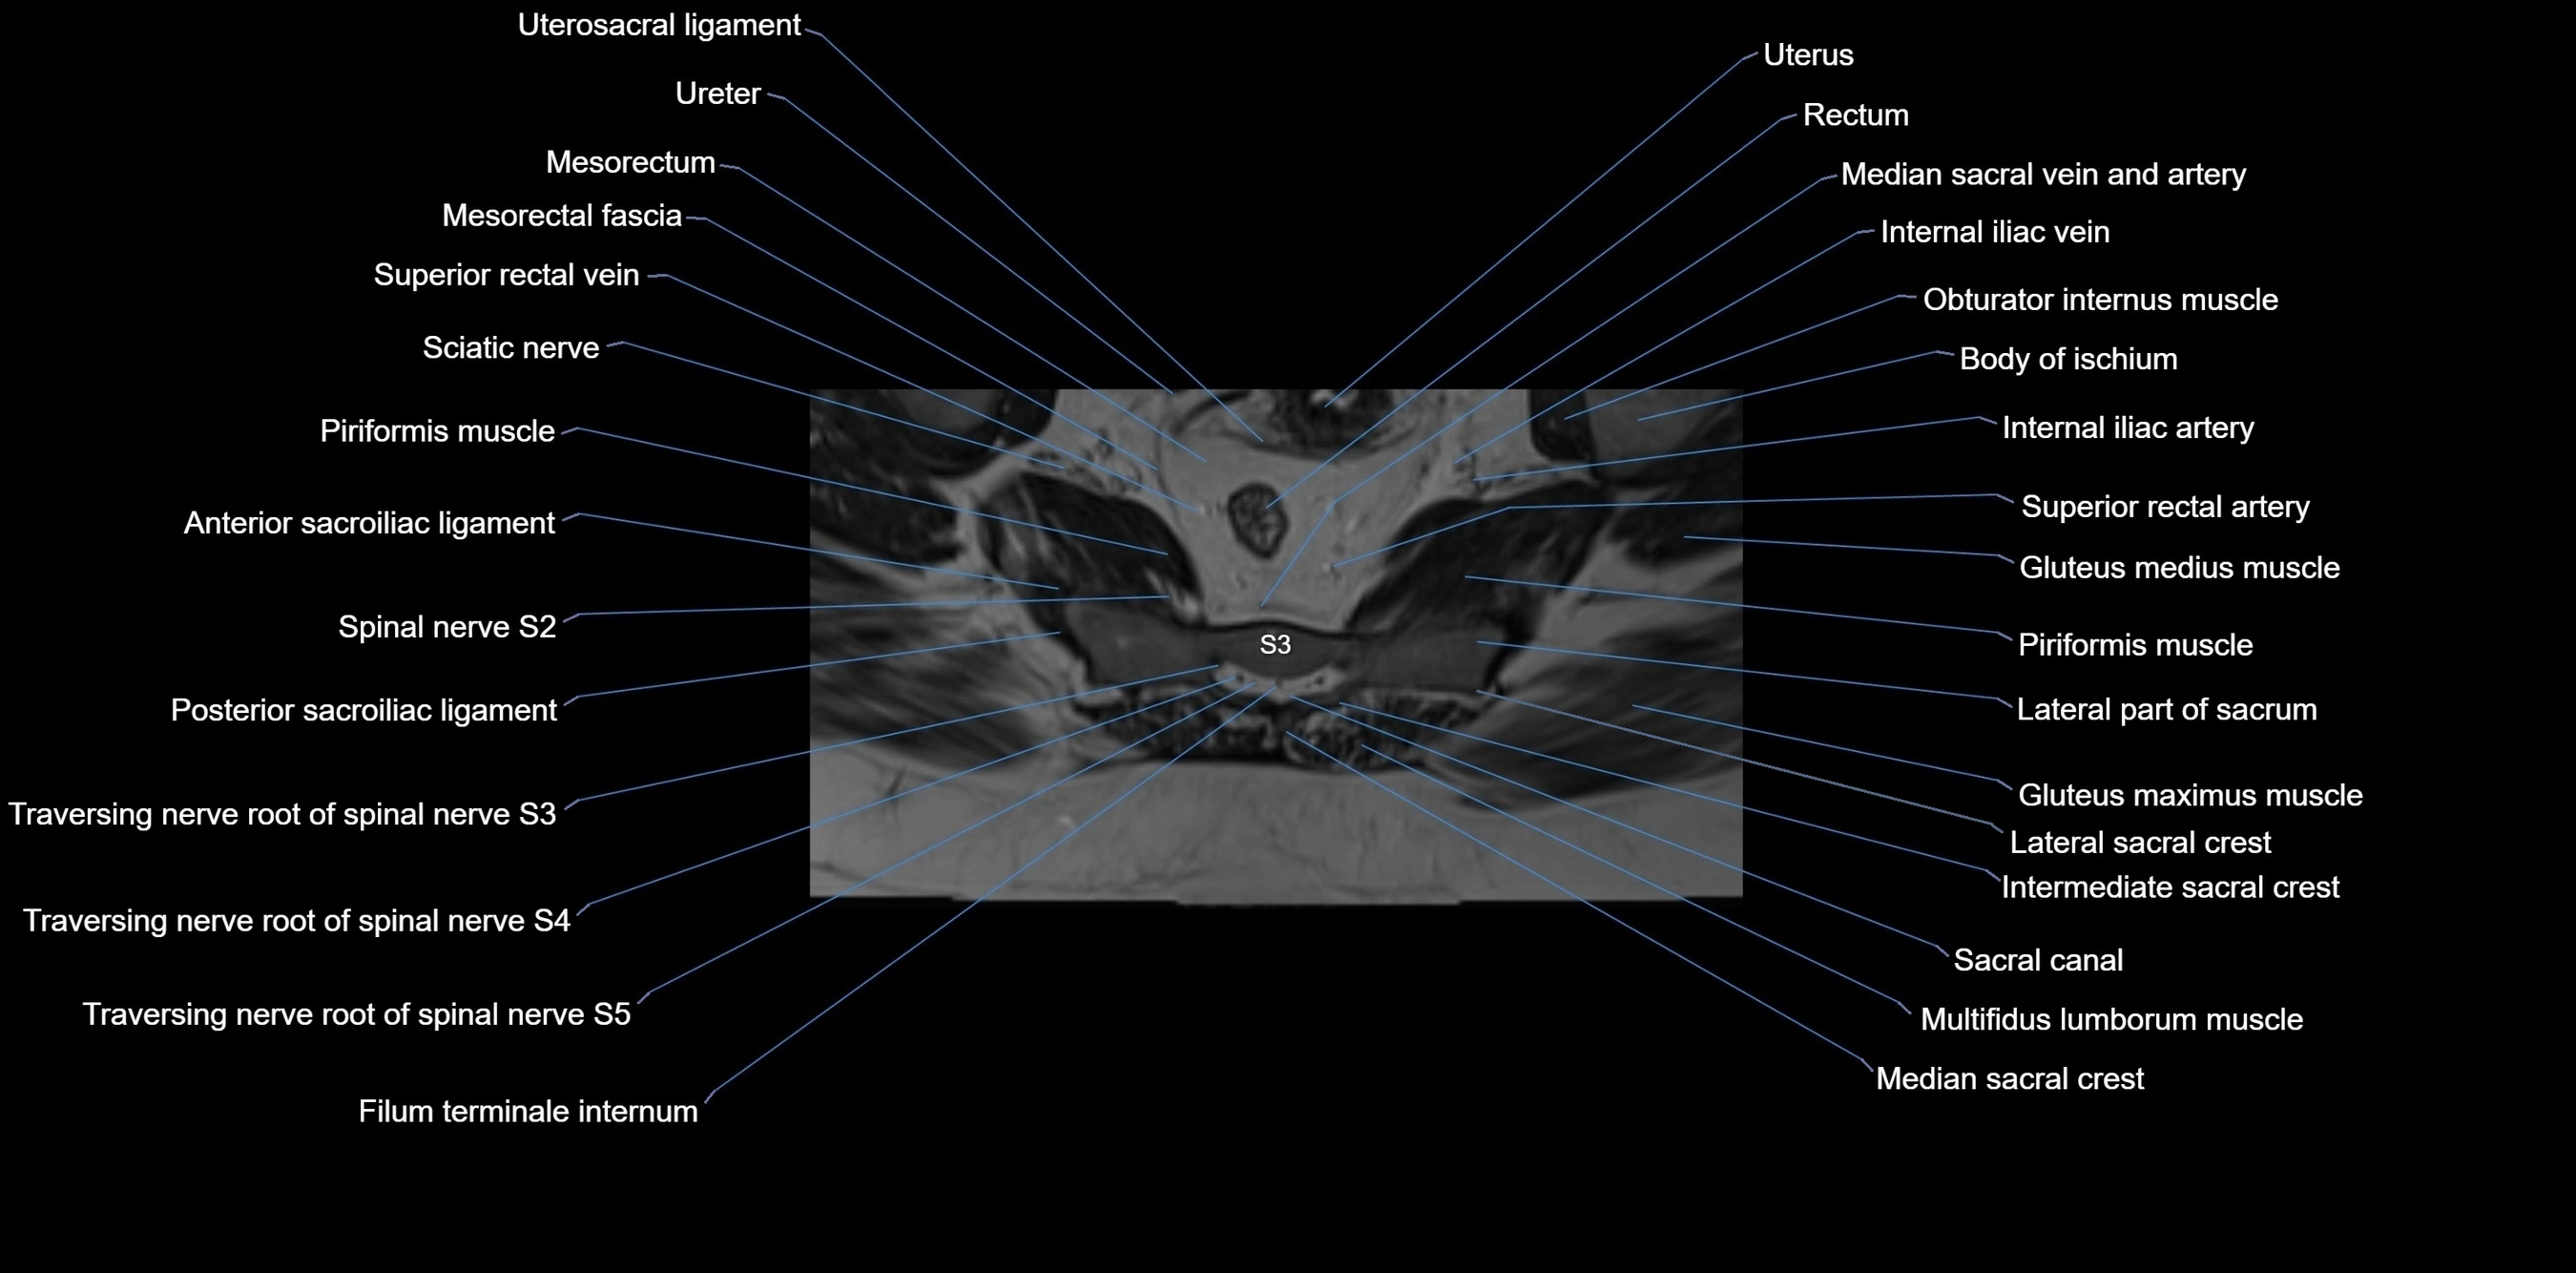

MRI Appearance

T1-weighted images:

• Cortical bone appears very low signal (dark); marrow shows intermediate signal

• Iliac fossa fat is bright against low-signal cortex

T2-weighted images:

• Cortical bone remains dark

• Marrow signal varies depending on fat content; edema or tumor shows hyperintensity

STIR:

• Suppresses fat, making bone marrow edema, fractures, or infiltrative lesions appear bright

• Excellent for trauma, sacroiliitis, and metastatic evaluation

T1 Fat-Saturated (Pre-contrast):

• Marrow: intermediate signal, fat suppressed

• Useful for detecting subtle marrow abnormalities adjacent to iliac cortex

T1 Fat-Saturated Post-Contrast (Gadolinium):

• Enhances vascularized structures, marrow pathology, tumors, and inflammatory changes

• Highlights soft tissue or bone invasion in pelvic neoplasms

MRI Non-Contrast 3D Imaging:

• Provides 3D morphology of iliac wing, crest, and articulations

• Used in preoperative planning for pelvic surgery and trauma reconstruction

MRI image

image